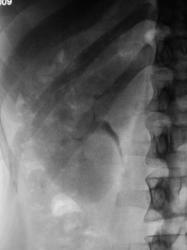

Почки контурируются в типичном месте, обычной формы и размеры. R-позитивных уроконкрементов в проекции мочевыносящих путей на обзорной урограмме не выявлено. ЧЛС контрастированы синхронно, не расширены. Мочеточники контрастированы, левый просматривается на всем протяжении, в нижней 1/3 незначительно стойко расширен, оттеснен кверху и вправо (хотя возможен такой вариант расположения устьев мочеточников - к сожалению правый мочеточник не визуализируется т.е. несчем сравнить). В мочевом пузыре, слева от срединной линии, дефект наполнения с четкой неровной границей.

Не хватает клинических данных (хотя бы укажите с какой стороны болит?) и других изображений контрастированного мочевого пузыря (необходимо выяснить стойкий это дефект наполнения или нет).

Что же касается визуального сужения мочеточника, указанное уважаемым Ореховым, то это можно считать как огибание поясничной мышцы, и незначительный ретроградный ход мочеточника.

"Расширение н/3 мочеточника "- если ширина данного участка мочеточника на самом деле более 13мм то да можно считать это расширением, а визуально выглядит как гипотония мочеточника, часто это собравождается наличием рентген- или нерентген-контрастного камня в устье или н/3 мочеточника.

Меня немного смутило сужение мочеточника у левой почки, возможно перистальтика. Прошу обратить внимание.